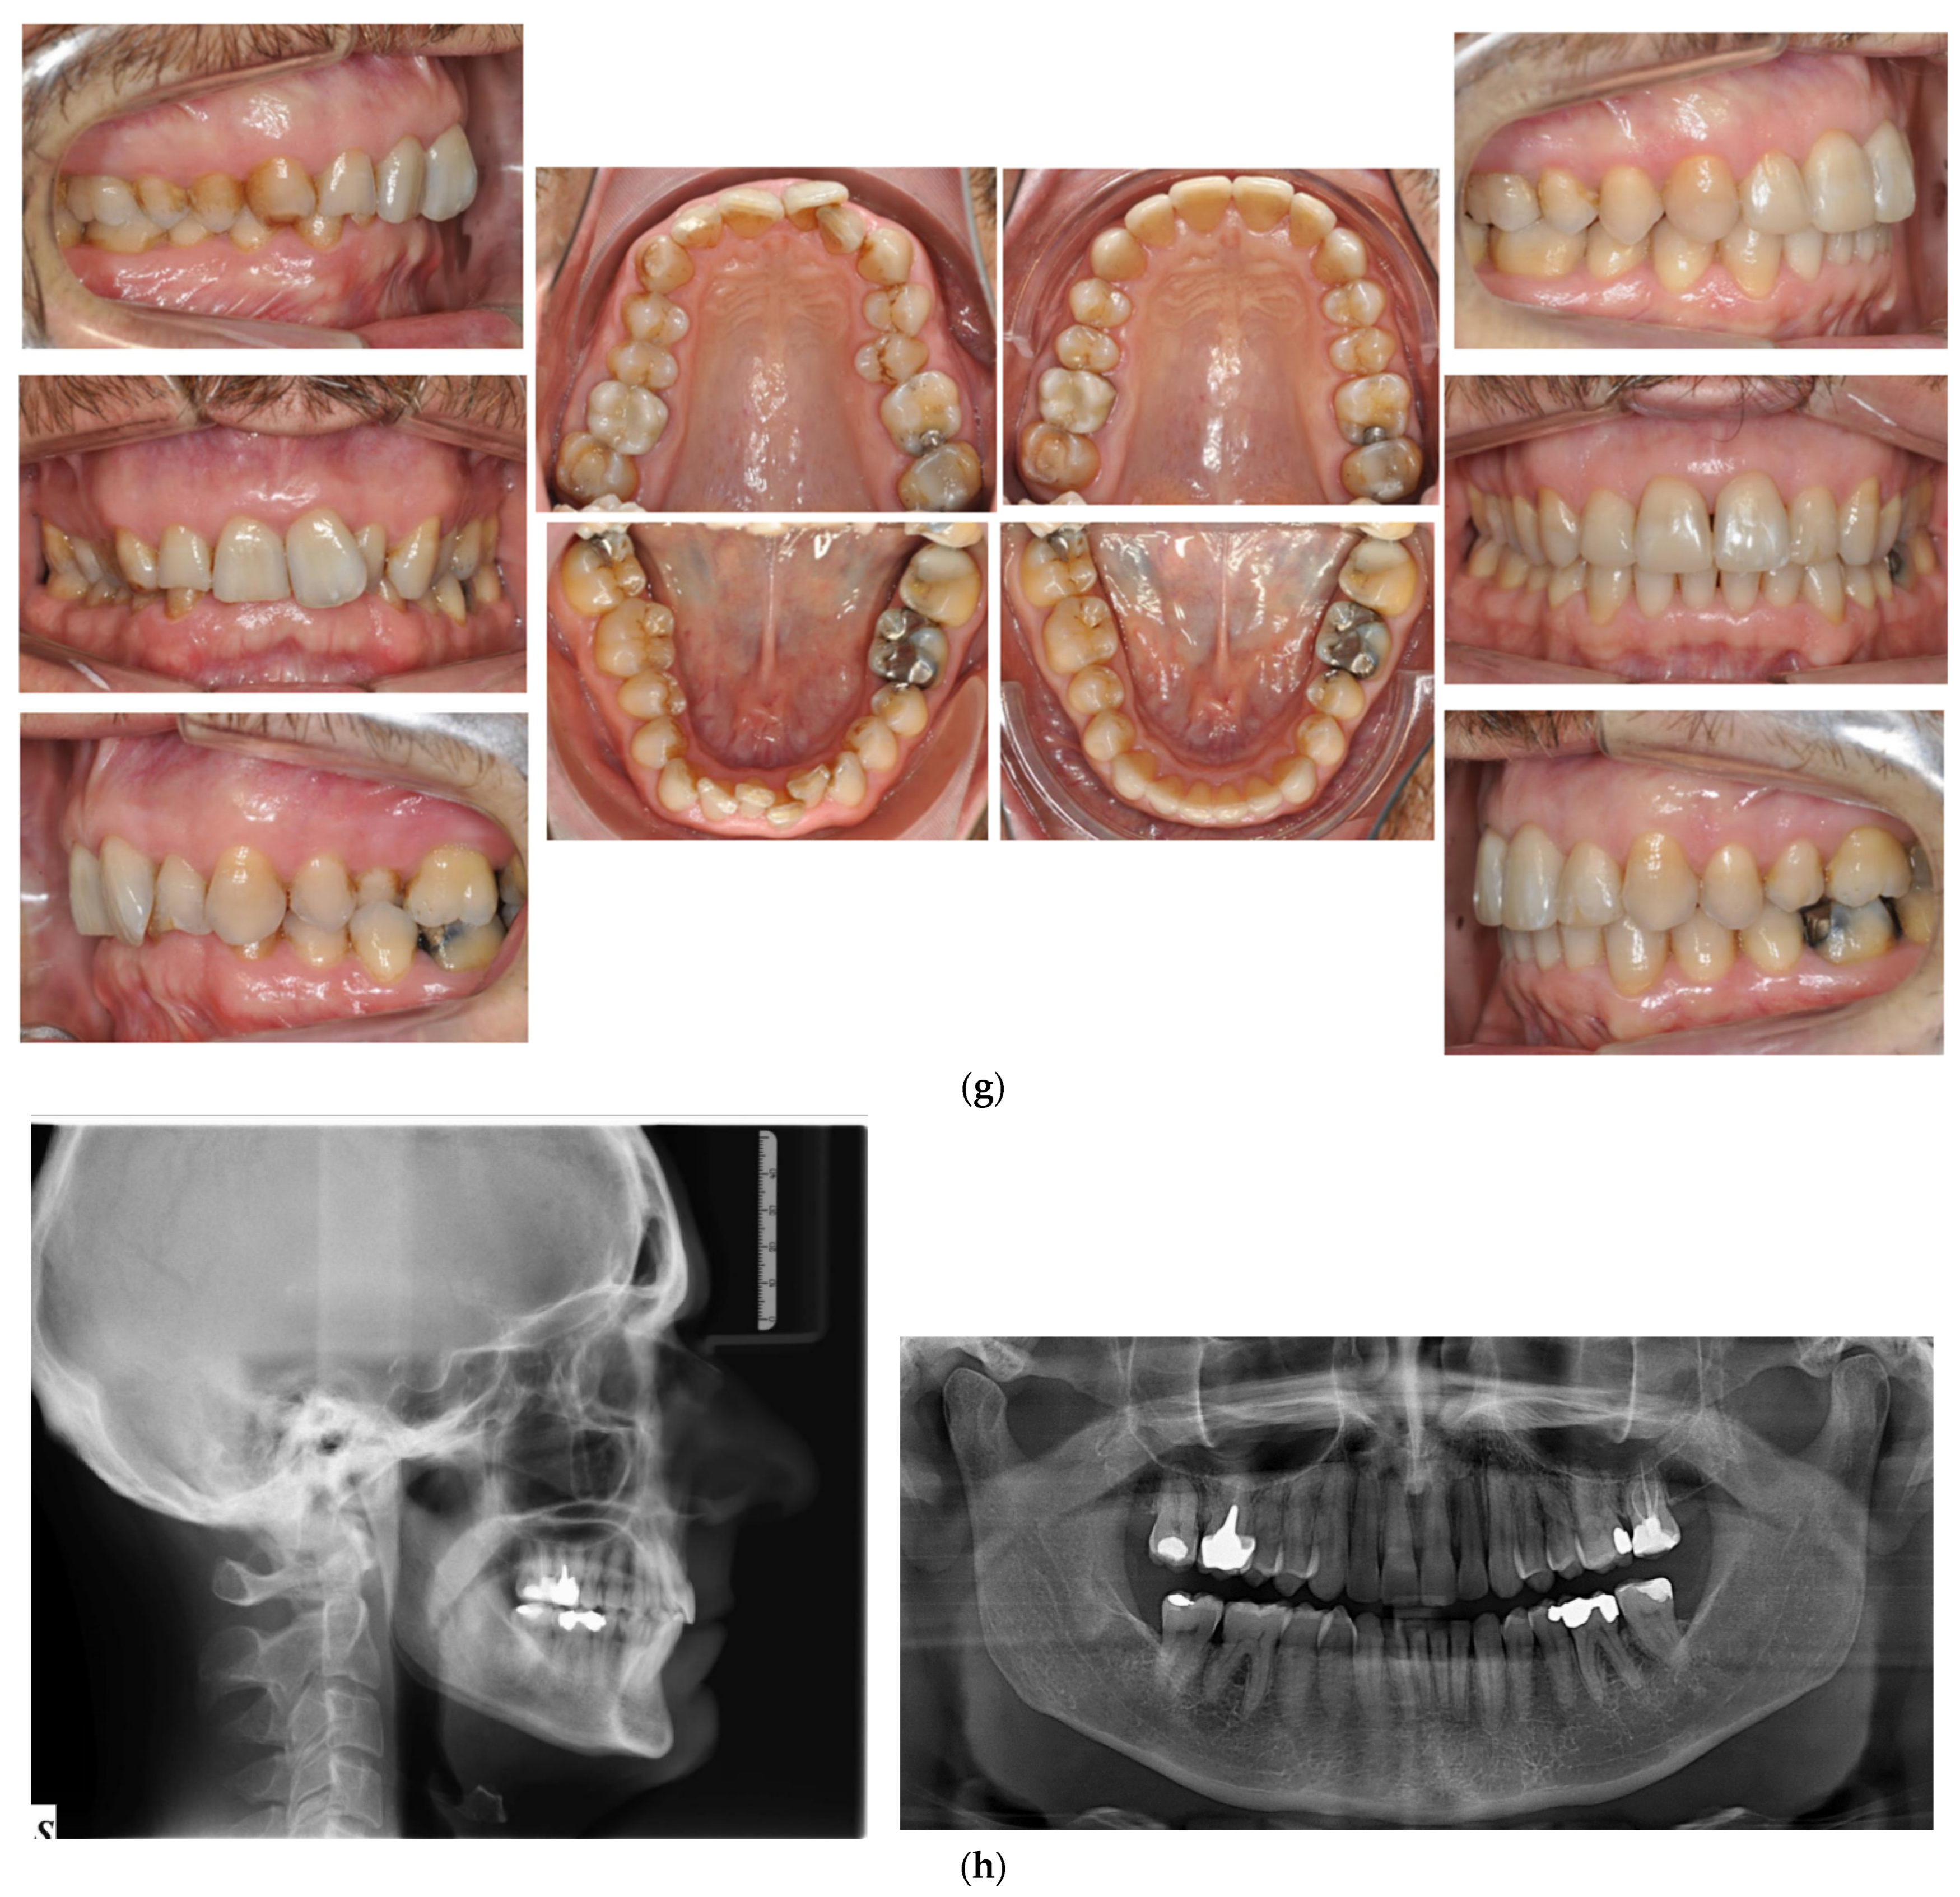

Figure 5.

(a,b) The initial images of the profile and frontal smile view and intraoral images and radiographs, including panoramic radiographs and a lateral cephalogram. (c) The digital setup performed for the treatment. (d,e) The treatment in progress with a Crozat appliance along with the aligners and lingual appliances. (f–h) Post-treatment images and a comparison with the initial images. (i) A superimposition of the pre- and post-treatment cephalograms.

After 18 months of active treatment, removable retainers were prescribed for both the upper and lower arches.

Although the correction of transverse discrepancies with good torque control is challenging with both lingual and aligner techniques [24,34,38], Case 3 (Figure 5) had a similarly successful outcome. In that case, the treatment required significant transverse expansion, along with the elimination of the deep bite and resolution of the crowding in both arches. A Crozat appliance and a partial aligner with a bite ramp/plane was used for the initial four months. Temporarily opening the posterior bite enhanced the expansive effect of the Crozat and facilitated levelling of the lower curve of Spee via the direct use of lingual appliances on the mandibular arch. The intermolar width in the upper arch was increased from 53.6 mm to 57 mm and in the lower arch from 46 mm to 48.7 mm.

Once the expansion and deep bite correction had been accomplished, lingual appliances were bonded to align the upper arch, control the upper anterior inclination and torque (perfecting the crossbite), perform intrusion and control the lower incisor inclination.